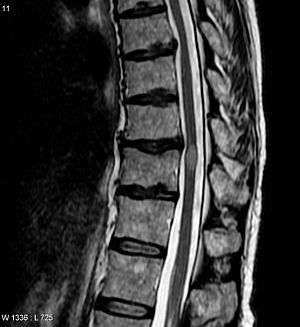

Myelitis has an extensive differential diagnosis. The type of onset (acute versus subacute/chronic) along with associated symptoms such as the presence of pain, constitutional symptoms that encompass fever, malaise, weight loss or a cutaneous rash may help identify the cause of myelitis. In order to establish a diagnosis of myelitis, one has to localize the spinal cord level, and exclude cerebral and neuromuscular diseases. Also a detailed medical history, a careful neurologic examination, and imaging studies using magnetic resonance imaging (MRI) are needed. In respect to the etiology of the process, further work-up would help identify the cause and guide treatment. Full spine MRI is warranted, especially with acute onset myelitis, to evaluate for structural lesions that may require surgical intervention, or disseminated disease.[9] Adding gadolinium further increases diagnostic sensitivity. A brain MRI may be needed to identify the extent of central nervous system (CNS) involvement. Lumbar puncture is important for the diagnosis of acute myelitis when a tumoral process, inflammatory or infectious etiology are suspected, or the MRI is normal or non-specific. Complementary blood tests are also of value in establishing a firm diagnosis. Rarely, a biopsy of a mass lesion may become necessary when the etiology is uncertain. However, in 15–30% of patients with subacute or chronic myelitis, a clear etiology is never uncovered and their condition is considered idiopathic.[5]